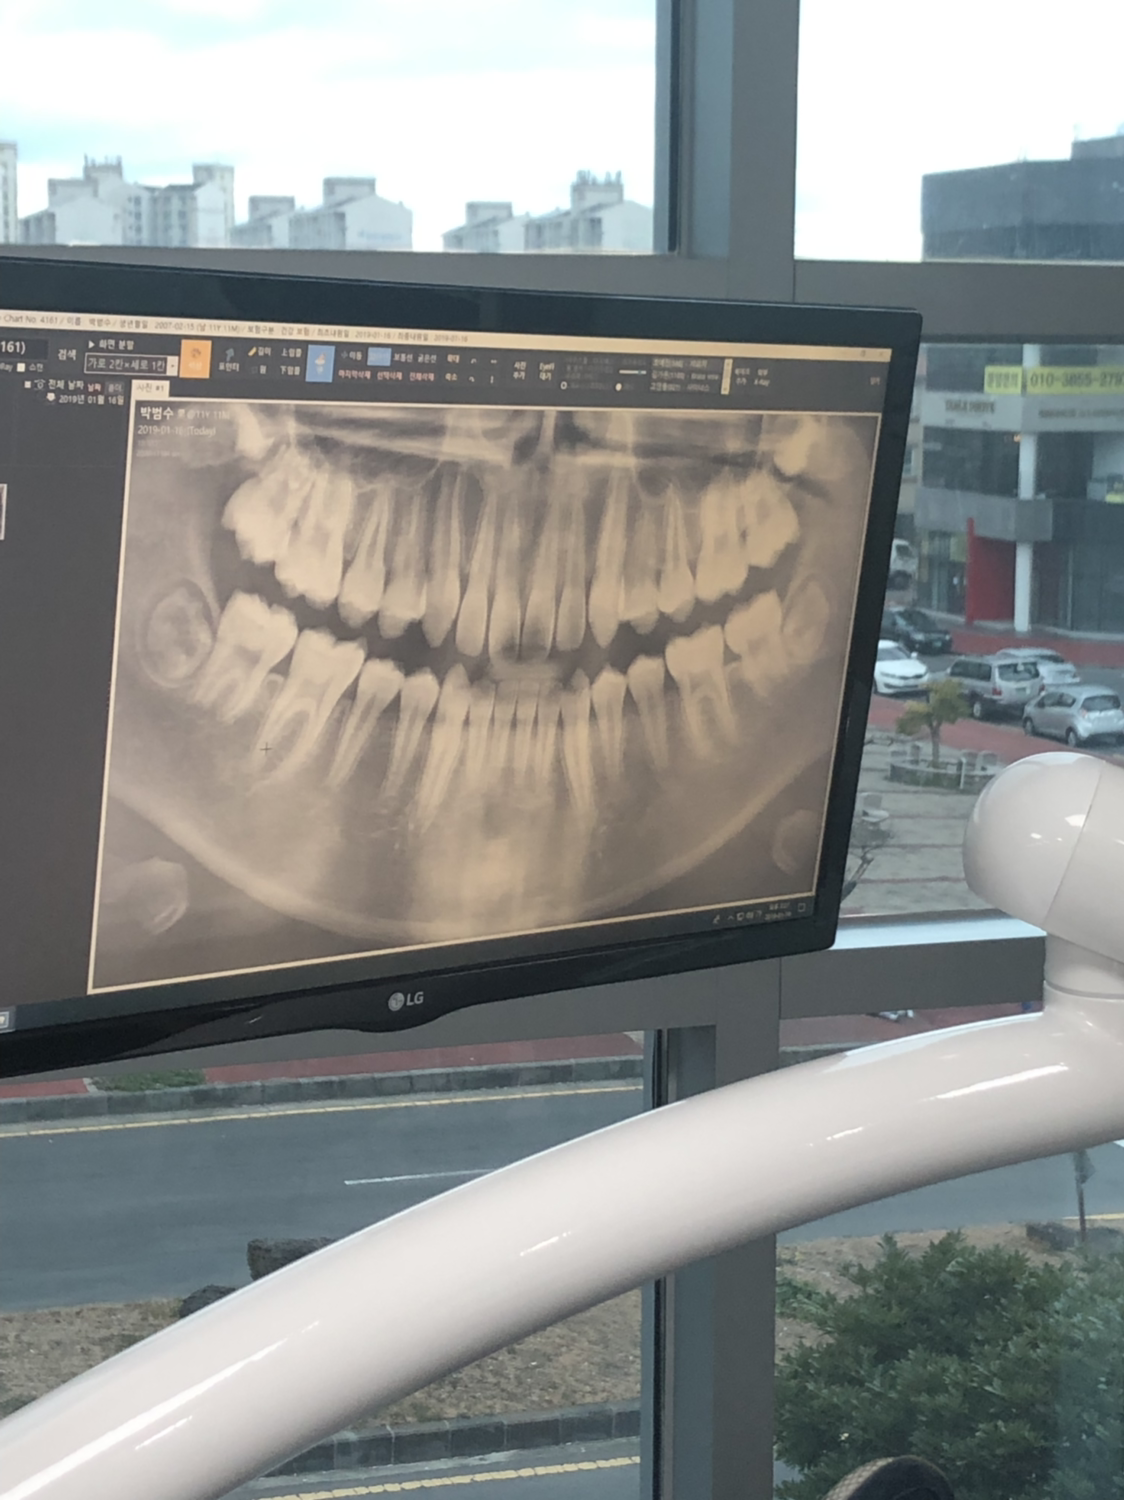

오후에는 치과 가기.

진료는 아이들이 받는데 옆에서 지켜보는 내가 진땀 난다. 애들 이가 성치 않은 것이 엄마가 잘 관리하지 않은 결과인것 같아 얼굴이 화끈 거린다.

아이들 치료가 아플까봐 옆에서 전전긍긍.

애들은 치료 잘 받았는데

진료 끝나고 나니 내 등이 축축하다.

지난 여름 방학에 치과 검진을 걸렀더니

충치 치료할 것이 많네.